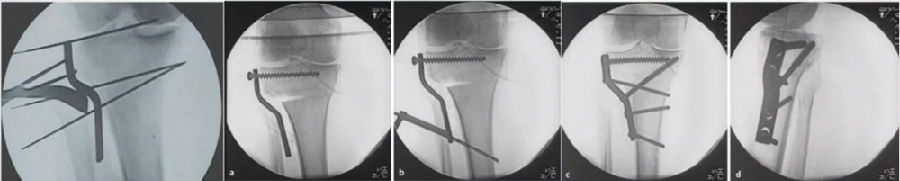

(3)Hybrid CWHTO

矫正角度过大,可采用Hybrid CWHTO,改变截骨合页点,有效避免CWHTO和OWHTO的缺点。

混合截骨

术中影像

结合影像学来看,该患者单纯用闭合截骨或开放截骨,对肢体均有影响,所以决定采用混合型截骨。术中混合截骨旋转中心选在内外1/3处,先做闭合楔,然后顺势将开放楔敲开,达到术前设计的目标力线。术后随访力线达到要求。

术后X线